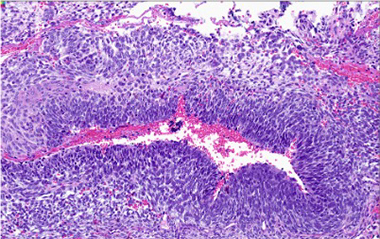

B. Complex cystic architecture (low power)

C. Pheochromocytoma with "zellballen" features

D. Pheochromocytoma

Pheochromocytoma was identified comprising 50% of tumor volume. In addition, the lesion contained a primitive round cell component possibly neuroblastoma with focal neuroblastic differentiation (20%) and a malignant peripheral nerve sheath tumor (30%) with heterologous elements (cartilage). Areas of hemorrhage and necrosis were noted resulting in cystic degeneration.

Microscopically, transition between the tumors may be blended or abrupt, pheochromocytoma is almost mostly the predominant pattern with apparent zellballen or variant patterns, GN contains ganglion cells in background of Schwann cells, GNB will have immature and maturing neurons, neuropil and Schwann cells, NB will have small round blue cells and MPNST will show malignant spindle cells with high mitotic count. Note that to designate as composite, although there is no precise portion of the components specified as a definition, there must be complete tumor patterns and not just scattered neurons. Overall, patterns of growth, intermixed cellular components, and immunohistochemistry usually allow this tumors separation from its differential diagnoses.